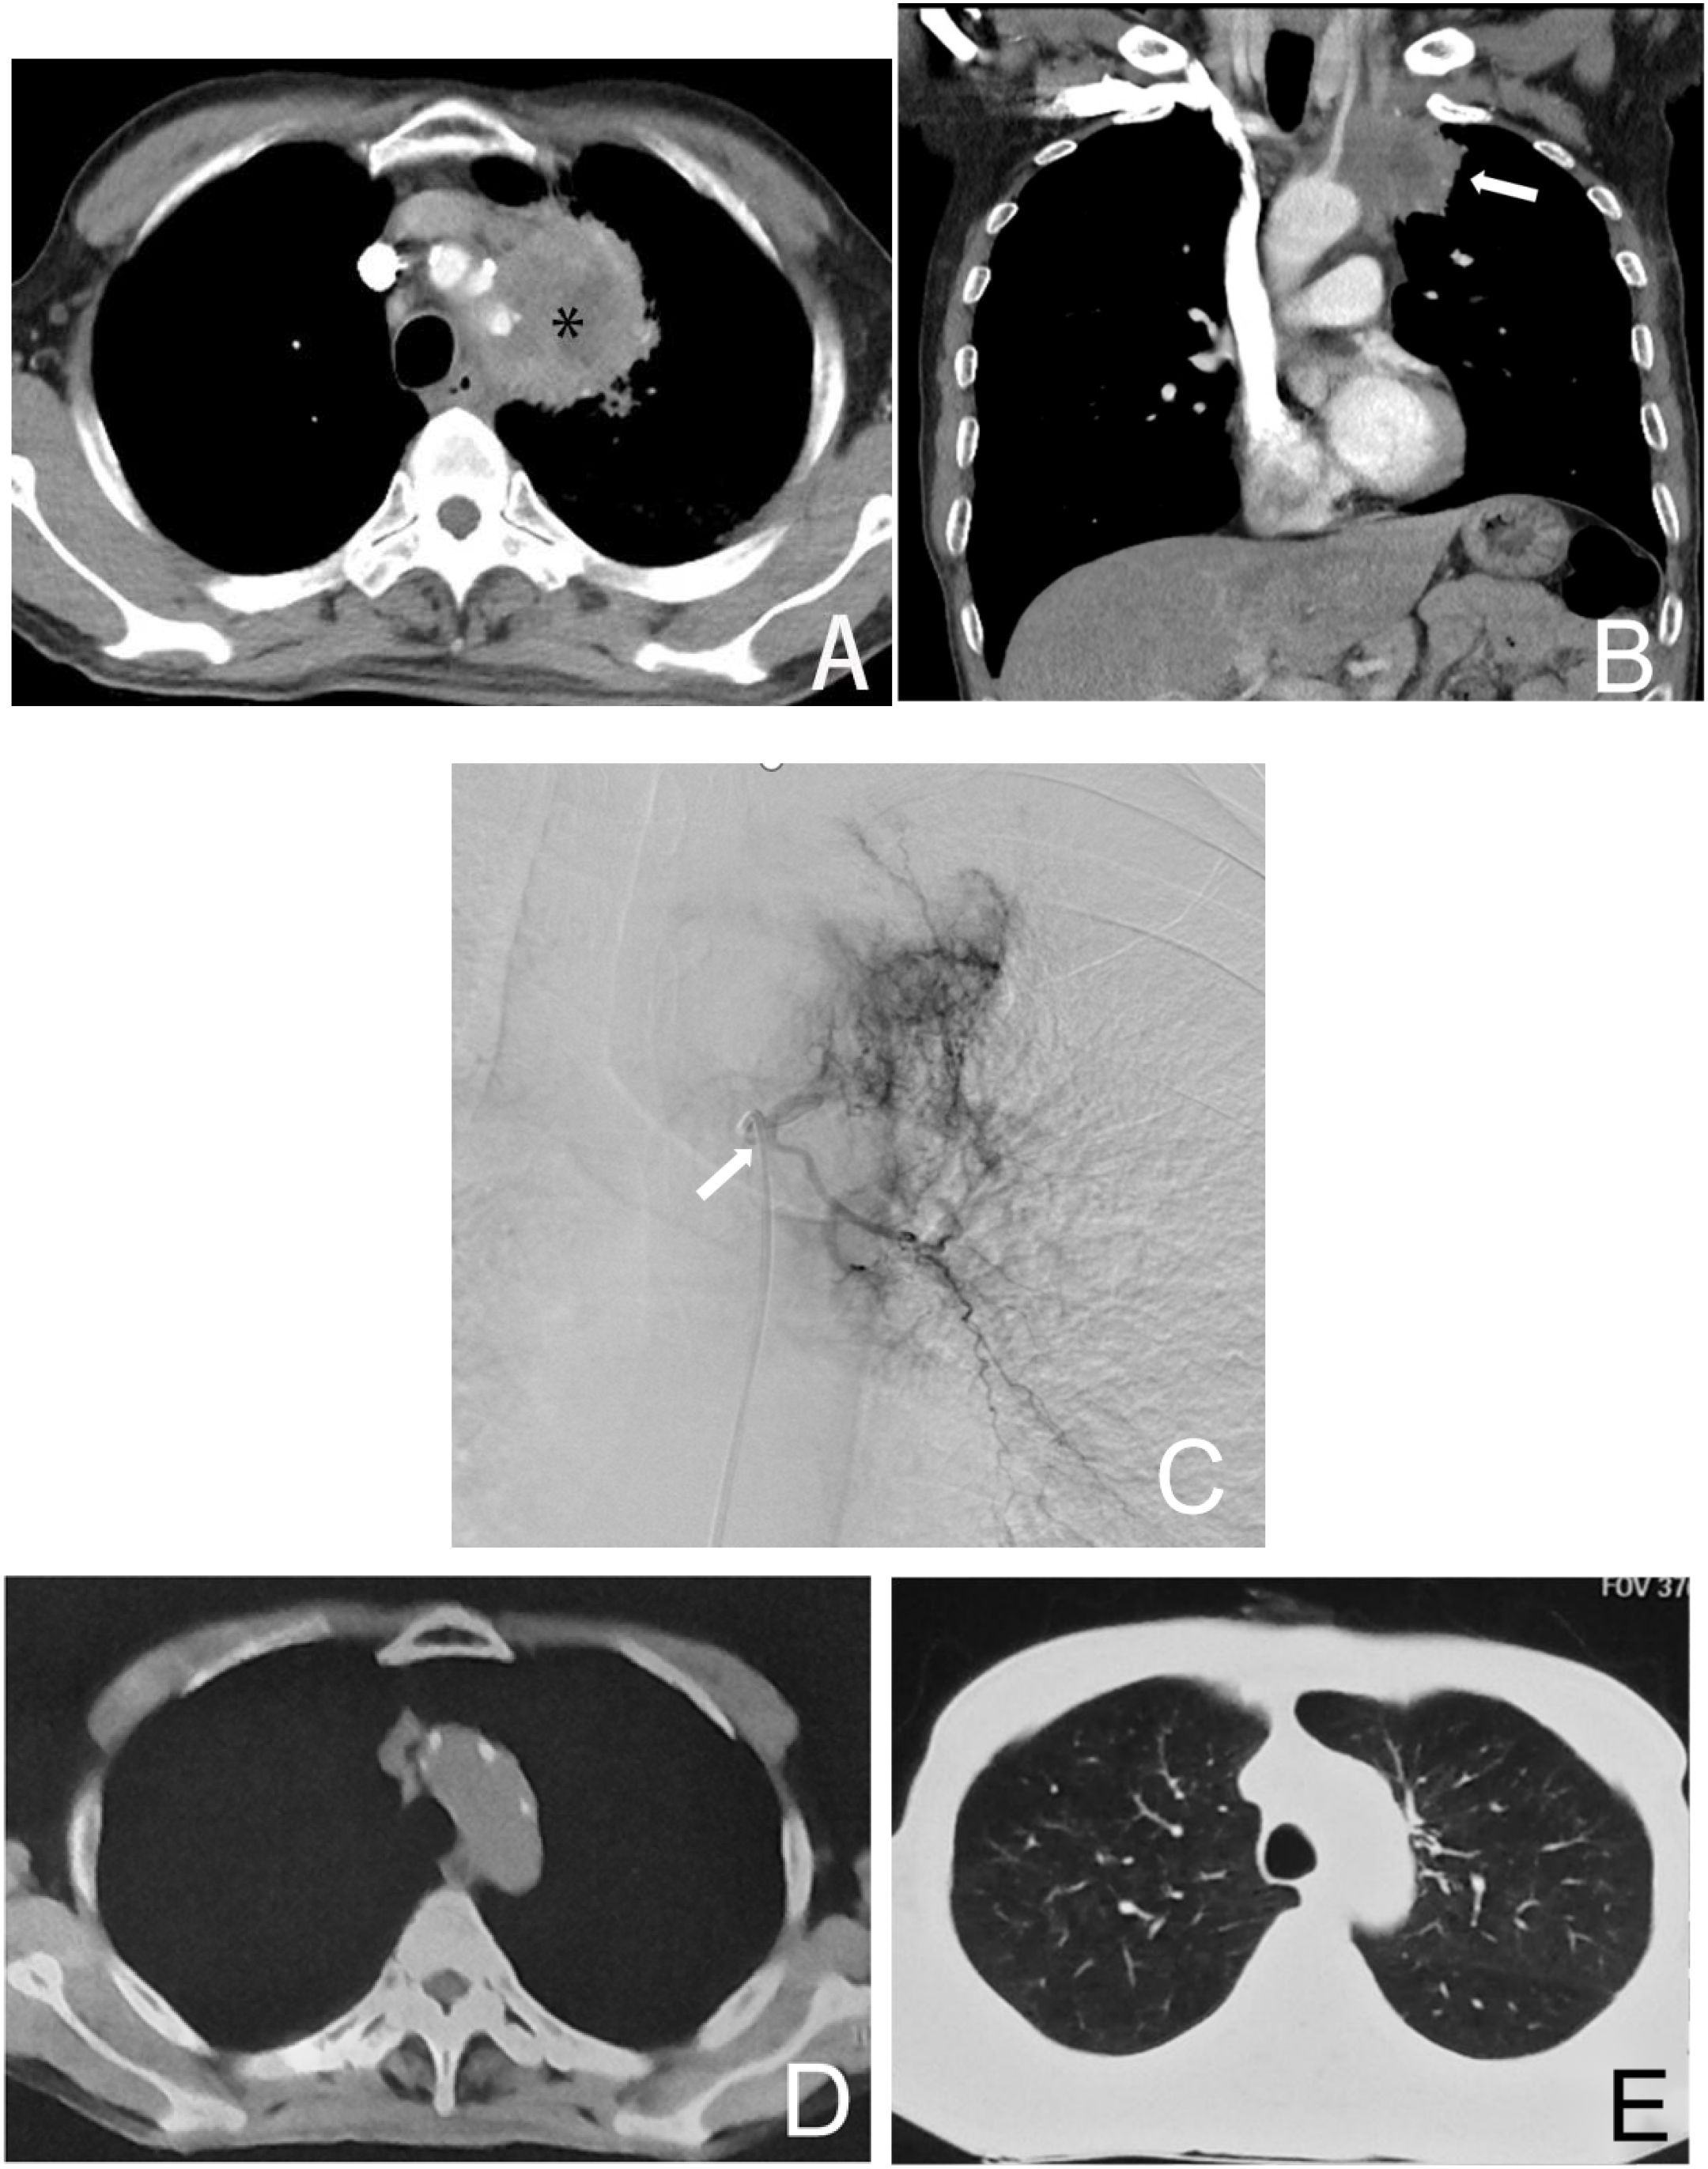

This study compares the relative advantages and safety of BACE versus systemic chemotherapy in patients with non-small cell lung cancer (NSCLC) (25). By directly targeting the tumor’s blood supply arteries, BACE is able to more effectively control local tumor growth, making it particularly suitable for patients with inoperable lung cancer (Figure 3) (6, 12–15). The advantage of BACE in partial remission rate and objective response rate may be attributed to its localized high concentration chemotherapy agents directly targeting the tumor area. The BACE group showed significantly higher rates of relief in cough and hemoptysis compared to the chemotherapy group (P = 0.028 and 0.001, respectively), and also exhibited better relief of dyspnea (71.9% vs. 60.0%, P = 0.077). Overall, BACE showed satisfactory improvement in major symptoms in patients.

Figure 3. Male, 61 years old, diagnosed with left lung adenocarcinoma through a puncture biopsy, without driver mutations (no molecularly targeted therapy). Figure (A) shows the CT axial image of the chest, where the left upper lung cancer surrounds a major blood vessel, making it inoperable (*). Figure (B) shows the coronal image of the patient, indicating the left lung tumor (→). Figure (C) is a left bronchial arteriogram showing that the left lung tumor was supplied by the left bronchial artery with a rich blood supply (→). Figures (D, E) demonstrate that after four courses of BACE treatment, the tumor has disappeared, with the treatment achieving CR.